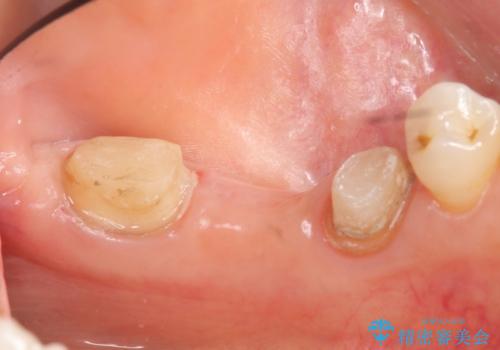

骨の定着を待ちポケットが3mm(正常範囲内)であることを確認後、オールセラミッククラウンによる欠損補綴を行いました。

今回用いたオールセラミッククラウンはジルコニアフレームという白い素材の上にセラミックを盛っているため、審美性が非常に高いのが特徴です。

また、ジルコニアは人工ダイヤモンドの材料にも使われているほど高い強度を持っており、そのためオールセラミッククラウンは審美性だけでなく、奥歯やブリッジの補綴も可能とするクラウンです。